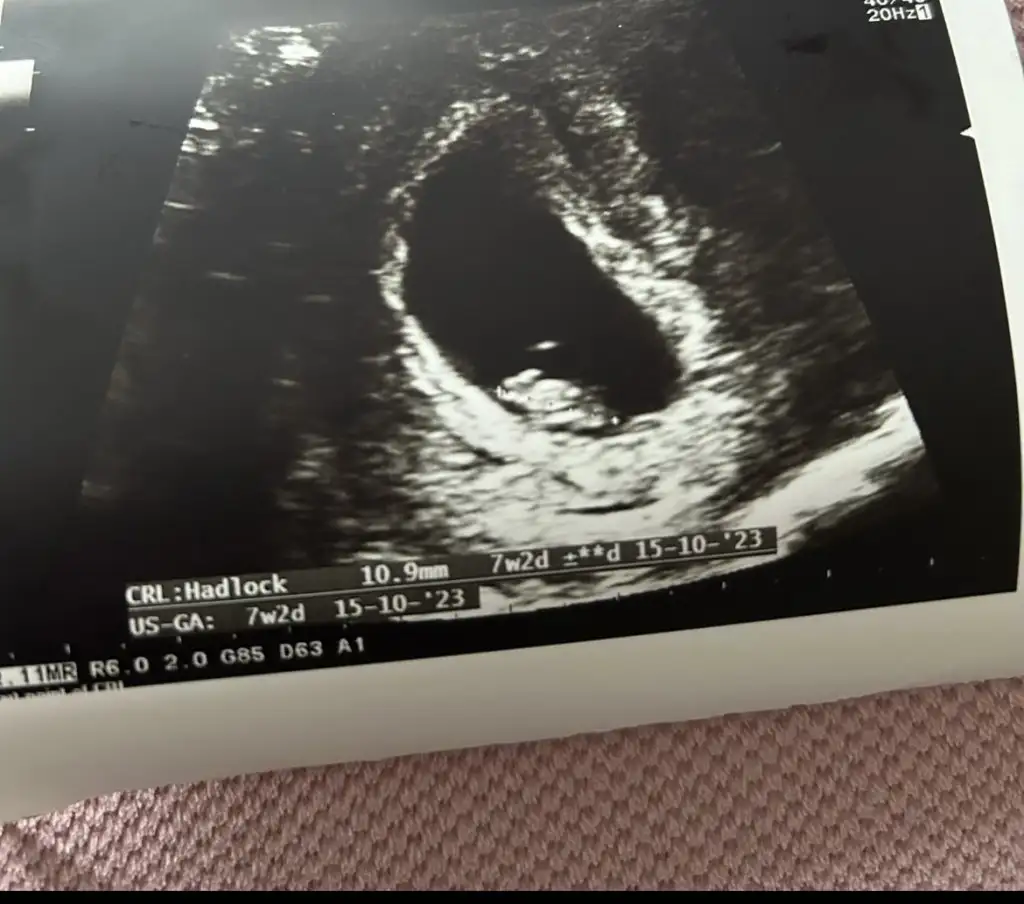

Kızlar ben bugün çok kasık ağrısı yaşadım daha önce düşüğüm olduğu için eşimle çok korktuk ve ilk defa muayeneye gittik keseyi gördük ama çok küçüktü ve şekli biraz farlı doktor 2 hafta sonra tekrar gelin dedi sizde bir bakarmısınız sat a göre bugün 6 haftalık